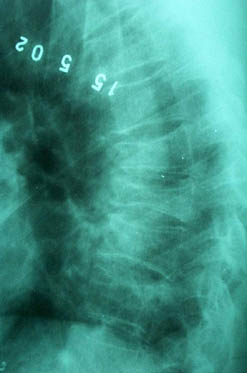

Уважаемые участники форума, Больной 53 лет, с жалобами на выраженные боли в области грудного отдела позвоночника, чувство онемения и стягивания в правой кисти, боли в мышцах конечностей и туловища. Отмечается парез правой верхней конечности.

В декабре 99 года перенес геморрагический а потом и ишемический инсульт левой задне-лобно-височной области. Выписался со значителсным улучшением неврологической симптоматики. Через год, на фоне обычного самочувствия, пожаловался на боль в спине, после чего появилось тоническое напряжение правой руки, половины туловища, перерастающее в приступ с судорогами по типутонико-клонических и потерей сознания. Госпитализирован. На CТ выявлен большой очаг в виде кистозной полости. Компрессионный перелом 8-9 грудных позвонков. В последующем, на протяжении полутора лет в общей сложности отмечено 5 аналогичных по формуле припадков. Падения с высоты во время приступов небыло. Также отрицает травмы позвоночника в анамнезе. ПовторнаяR-графия и СТ позвоночника выявила патологический компрессионный перелом и остеопороз тел Th 6; 7; 8; 9, (отрицательная динамика). Наличиенеобластомного процесса не выявлено. Все анализы, включая паратгормон, впределах нормы кроме:Са-Т - 2.66 (от 2.02 до 2.60)Р - 1.72 (от 081 до 1.62)СОЭ - 34мм/часСнимки 1, 2, 3, 4 прилагаются.Возникает ряд вопросиов: Может ли деструкция в левой задне-лобно-височной области быть связана с системним остеопорозм позвонков и пат. переломом? Моигут ли эпилптические приступы явиться причиной компрессионного переломапозвонков? Какие дополнительные исследования нужны для дифдиагностики болезни Куммелля? Тактика лечения (корсет?), показания и противопоказания к хирургическому вмешательству на позвонках в данной ситуации Прогноз?Буду благодарен любым соображениям,Аршак Мирзоян